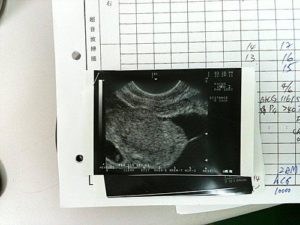

n October 28th, 2010, my little girl was born being 2800 kilograms, and I waited for her so long…………

When Doctor Chang announced me as the winner, my husband and I cried with joys, and we finally arrived at our happy ending…

My husband, always opposed my decision of receiving test tube treatment, became very anxious and kept asking me: “You’re pregnant, really?”…………

This is a completely new day for both my husband and I, because we have been looking forward every month for the past ten years………….